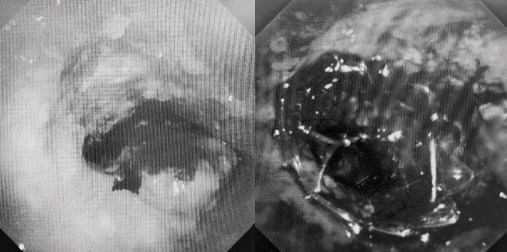

時間就是生命!了解患者病情后,歐陽海峰立刻啟動氣道梗阻緊急救治通道,協(xié)調(diào)院前轉(zhuǎn)運,急診快速入院流程。凌晨患者入院胸部CT顯示,現(xiàn)存唯一的呼吸通道在右主支氣管處,狹窄處僅約3毫米,患者命懸一線!

運用呼吸介入技術(shù),軟硬鏡結(jié)合快速開通氣道,是患者目前唯一可行的治療方案,手術(shù)刻不容緩!但存在麻醉后氣道完全塌陷閉合、大出血、窒息等巨大風(fēng)險。患者此前接連轉(zhuǎn)診3家醫(yī)院,均建議保守支持治療或轉(zhuǎn)院。歐陽海峰詳細了解患者病史,全面評估影像檢查結(jié)果后,決定盡快進行手術(shù),組織醫(yī)護團隊對患者進行持續(xù)密切監(jiān)測,充分保障其術(shù)前安全。

患者入院第二天,在麻醉手術(shù)中心全力配合下,歐陽海峰帶領(lǐng)呼吸介入團隊,歷時40分鐘快速置入硬質(zhì)支氣管鏡、鏟切腫瘤,并順利植入全覆膜TTS支氣管金屬支架。患者氣短癥狀即刻緩解,為患者贏得了寶貴的后續(xù)治療機會。